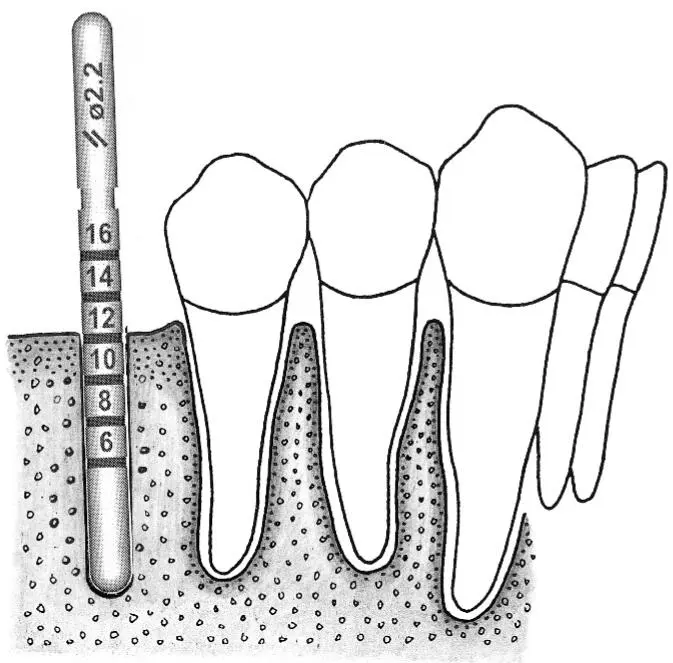

Fig 1-5Varying sink depths.

Fig 1-5a The 3.5-mm-diameter depth gauge is inserted so that the middle of the 12-mm mark is aligned with the bone crest (left) . When the standard implant is inserted, this allows the rough border to be aligned exactly at the crest (right) .